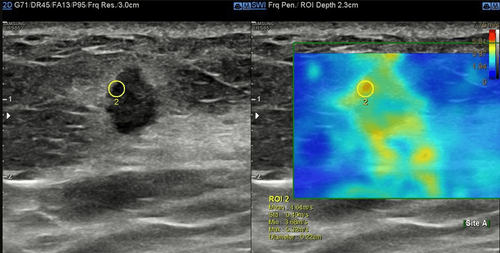

Trong bệnh lý tuyến vú, siêu âm tuyến vú bằng phương pháp đàn hồi mô có tác dụng hỗ trợ phân biệt khối u lành tính và ác tính, giúp hạn chế việc sinh thiết không cần thiết.

Siêu âm đàn hồi mô là kỹ thuật siêu âm giúp cho bác sĩ đánh giá được độ cứng của mô thông qua mức độ đàn hồi của mô khi chịu một tác động của lực cơ học. Các mô bệnh lý có thể cùng độ hồi âm, nhưng sẽ có độ cứng khác nhau, các mô càng ác tính thì độ cứng sẽ càng tăng lên. Chính vì thế, khi đánh giá được độ cứng của mô tổn thương sẽ cung cấp thêm thông tin về bản chất của mô đó.

Phương pháp siêu âm đàn hồi mô bằng cách tác động một lực từ bên ngoài lên tổn thương để gây ra biến dạng tổn thương như trên được gọi là tạo hình đàn hồi bán tĩnh hay còn gọi là đàn hồi gây biến hình. Khi thực hiện kỹ thuật, người làm siêu âm ấn đầu dò bằng một lực nhất định để tác động lên mô tổn thương.

Trong bệnh lý tuyến vú, siêu âm tuyến vú bằng phương pháp đàn hồi mô có tác dụng hỗ trợ phân biệt khối u lành tính và ác tính, giúp cho việc hạn chế sinh thiết không cần thiết.

● Bước 4: Kỹ thuật thực hiện trong khoảng 5 đến 10 phút. Đầu dò siêu âm sẽ thu nhận và mã hóa ra sóng bằng màu sắc giúp bác sĩ lượng hóa được độ cứng của mô.